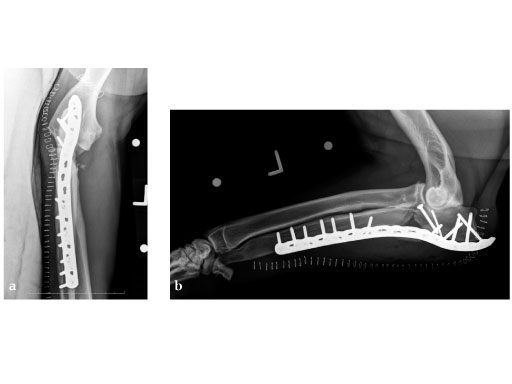

The LCP 3.5 broad plate is indicated for long bone fractures in large breed dogs.

This plate is similar to the standard human LCP, except for a central, stacked combination hole at one end, designed to facilitate treatment of metaphyseal fractures.

The LCP broad plate 3.5 system includes 14 plates with lengths ranging from 7 to 22 staggered holes. It can be used with 3.5 mm cortical screws (either locking head or standard) as well as 4.0 cancellous bone screws. This offers greater versatility than conventional plates. The implant material is 316L stainless steel. The plates are housed in the small fragment plate set graphic case. No additional instruments or screws are needed.

5-year-old male English Mastiff, road traffic accident.

(Case provided by Michael P Kowaleski, North Grafton, USA)